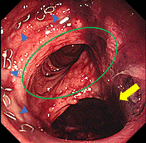

Cases of low anterior resection and ileostomy for rectal cancer that required more than 18 months for stoma closure

Yutaka Kojima and others

Journal of Surgical Case Reports, Volume 2019, Issue 5, May 2019, rjz153, https://doi.org/10.1093/jscr/rjz153